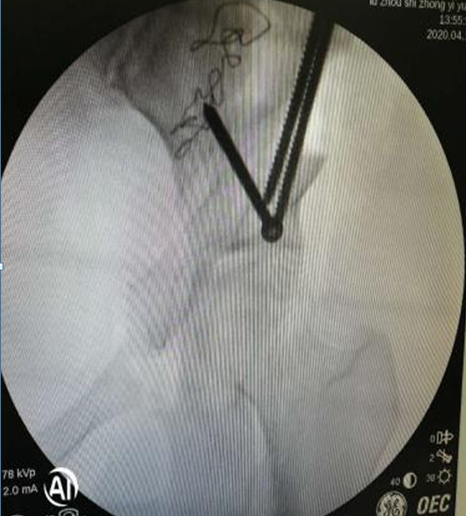

術(shù)中,左側(cè)髖臼周圍截骨

在李彬主任的帶領(lǐng)下,肖女士進(jìn)行了髖臼周圍截骨術(shù)PAO保髖治療:調(diào)整髖臼位置,使髖關(guān)節(jié)的旋轉(zhuǎn)中心適度內(nèi)移;增加髖臼對股骨頭的覆蓋,增加負(fù)重的關(guān)節(jié)面,降低了髖關(guān)節(jié)負(fù)重面軟骨的應(yīng)力,達(dá)到了延遲或阻斷髖關(guān)節(jié)炎進(jìn)展的目的,延長了自身髖關(guān)節(jié)的使用壽命。目前,患者恢復(fù)良好。

術(shù)后X光:CE角約26度,髖臼尺度正常